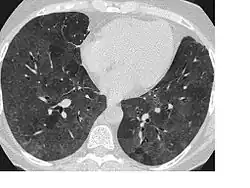

High-Resolution CT image in a patient with Pneumocystis pneumonia infection showing ground-glass opacities.